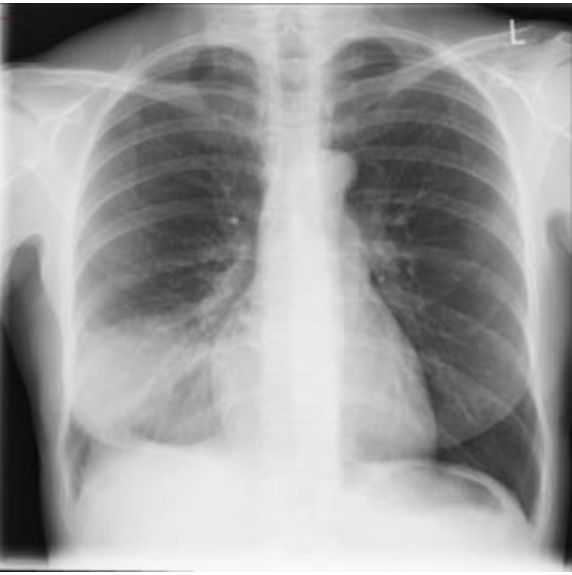

Ao exame: bom estado geral, embora abatida e com fácies de doença aguda. Corada, hidratada, anictérica, acianótica, eupneica. Ap Resp: MV universalmente audível, com estertoração crepitante em terço inferior à direita, onde se ausculta broncofonia. ACV, abdome e membros sem alterações. Sinais vitais: FC: 104 bpm; PA: 120/80 mmHg; FR: 20 irpm TAx: 39,0°C. Ao término do exame físico, foi submetida à radiografia de tórax, testes rápidos para Influenza e COVID-19 e coletada amostra de escarro para realização de bacterioscopia pelo método de Gram.

Os resultados evidenciaram:

Testes rápidos: COVID-19 – Negativo. / Influenza – Negativo.